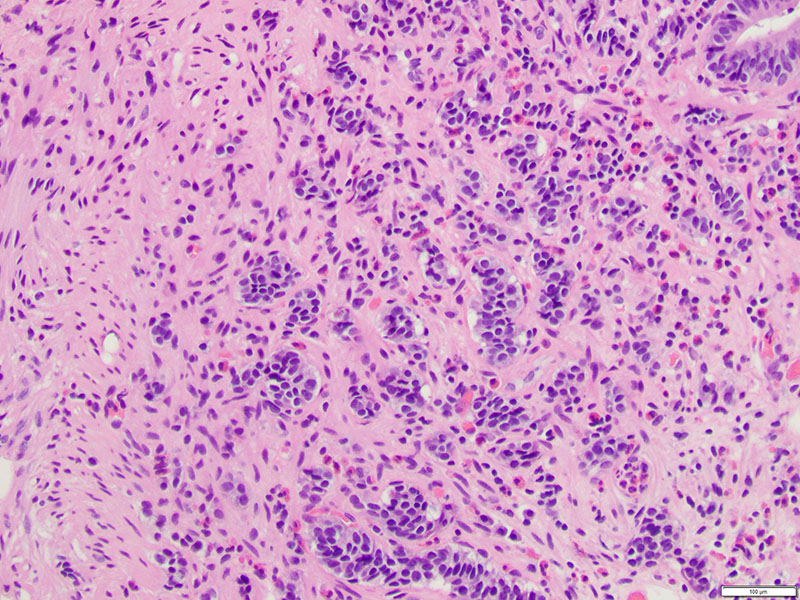

The patient is sent for an esophagogastroduodenoscopy (EGD), which reveals a 2 c.m. polyp in the third segment of the duodenum. Biopsy confirms duodenal adenoma, for which the patient elects to undergo an EGD with endoscopic mucosal resection (EMR).Microscopic examination demonstrates duodenal mucosa with low-grade epithelial dysplasia overlying foci of bland, monotonous cells with scant cytoplasm (Figures 1 & 2). The cells are arranged in nests and trabeculae that infiltrate into the superficial muscularis mucosae (Figure 3). Immunohistochemistry shows positive staining for synaptophysin (Figure 4) and chromogranin (Figure 5), as well as a Ki-67 labeling index < 1% (Figure 6).